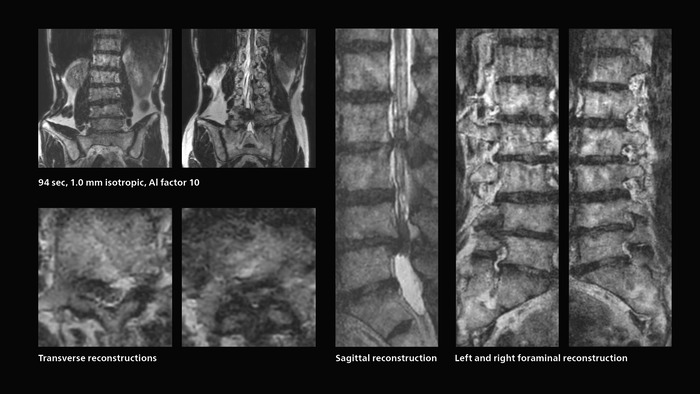

Many patients who must undergo a lumbar spine examination suffer from back pain. For these patients it is difficult to maintain the imaging position long enough to successfully complete the examination. “In such cases, using SmartSpeed allows us to perform volume imaging, so that we acquire only one high resolution 3D sequence in a short time and then reconstruct the other orientations from that,” Dr. Katahira says.

“This is highly advantageous because the patient needs only endure a short exam time, whereas before it was necessary to acquire a larger number of sequences in total. We have seen that the shorter time has allowed us to scan patients who previously could not finish the exam. This is a great advantage.”

Fast lumbar spine imaging for successful exam of patient in pain

A patient arrived saying that undergoing MRI was not possible because of severe back pain and leg pain, was imaged with SmartSpeed in only 94 seconds. The scan was diagnostic and afterwards the patient confirmed that it only took a little while. Performed on Elition X.

Fast lumbar spine MRI with SmartSpeed of a patient in pain produced a successful isotropic diagnostic scan in only 94 minutes.

The hospital’s fast lumbar spine ExamCard includes T2W SpineVIEW, 1:40 min, 1.0 mm isotropic, acceleration factor 12.